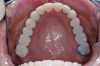

Figure 4  Interocclusal registration made at the approximate OVD for rehabilitation.

Figure 4

Figure 5  Accurate casts mounted at arbitrary OVD.

Figure 5